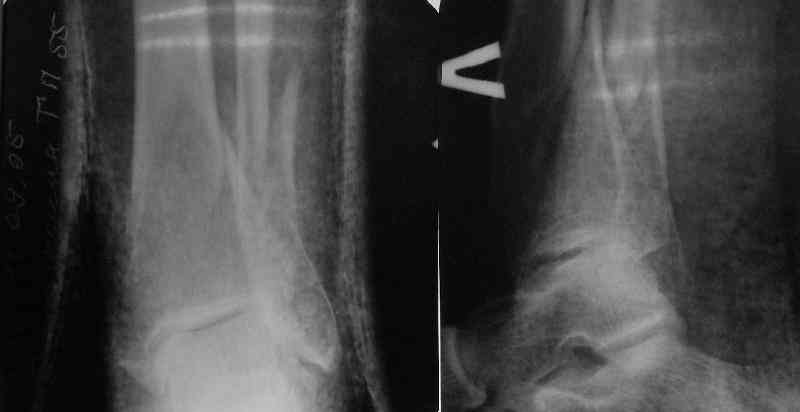

A typical case is attached, also an image with intra-op reduction obtained by a small wire distractor, in the moment of insertion a Poller wire in AP direction. Fixation by a SIGN nail. Despite the fibula was not fixed healing was obtained with the unchanged alignment.

Very interesting application, but is the final position in a little distal varus with some fibula

distraction? Would that have been eliminated by fibula plating?

At least both the ankle mortise and tibial alignment look acceptable, don't they?

I am just trying to illustrate that prevention of 1)tibial valgus and 2)loss of reduction can be provided without fibular plating. Small changes of conventional nailing techniques allow to maintain reduction of the tibia reliably without adjunctive fibular stabilization.